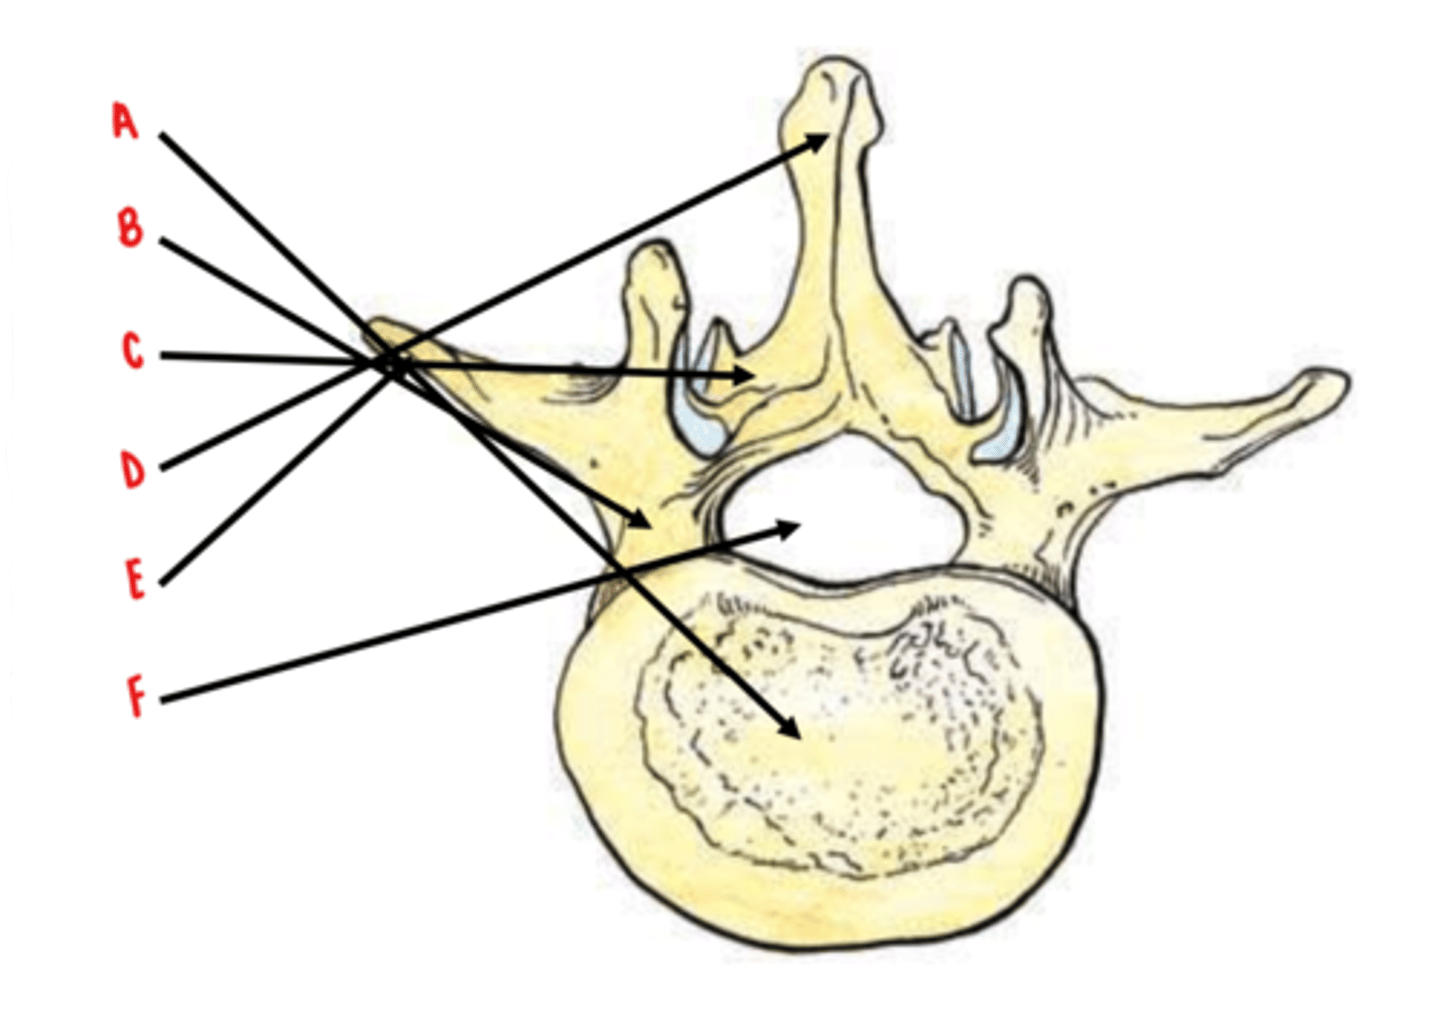

50 Terms

body

Identify A

pedicles

Identify B

laminae

Identify C

spinous process

Identify D

transverse process

Identify E

vertebral foramen

Identify F